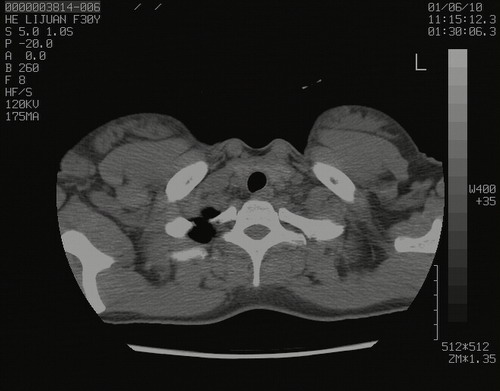

怀孕3个月时(2009-3至4月间),自述突感左侧前后胸疼痛1天,以前胸明显,随后偶感闷痛,余未见异

左肺尖脊柱旁沟肿块,境界清楚,边缘光滑,密度不均,内有多发点片状钙化,考虑良性肿瘤,骨软骨瘤或神经源性肿瘤可能,肺错构瘤不除外。

左后上纵隔见一类圆形肿块影,外侧边界清,密度不均匀,内可见点状钙化影,增强呈不均匀强化,考虑神经源性肿瘤可能。期待病理结果。